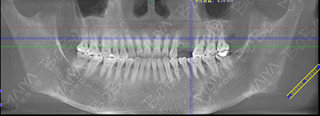

赵女士种牙前口腔全景ct

由于赵女士长期牙缺失,牙槽骨已经出现萎缩吸收,导致两边邻牙倾斜,因此她的牙缺失间隙在动态变小,牙齿的间隙不够种植两颗牙的位置,但是种一颗牙又显得空间有点偏大,最终游勤波院长和孙海鹏博士经综合考虑,采用麦芽数字化生物种植技术,数字化精准导航种植,采取了种植一颗连冠修复的方式,只需一颗种植钉就可以达到修复两颗牙齿的目的,仅仅不到一个小时就帮赵女士种上了牙齿。